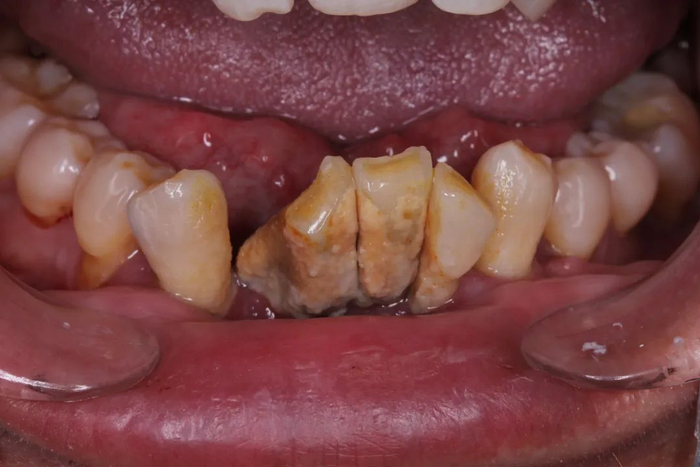

大量牙结石,导致牙齿松动移位,

再再后来,牙齿不仅仅松动了,它们可能还开始移动位置了——牙齿和牙齿之间的缝隙越来越大。而之前松动的牙齿开始摇摇晃晃,有的还会出现牙齿的疼痛!